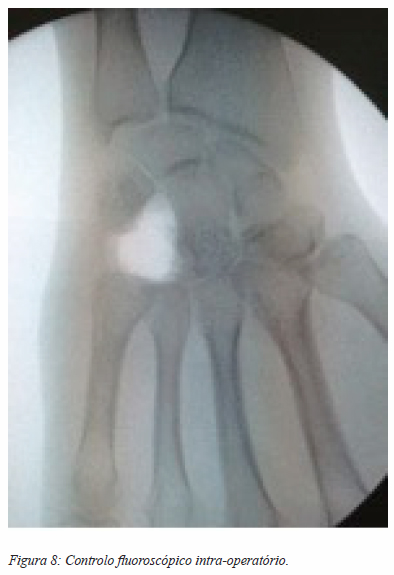

No dia 12 Março 2015 é submetida a exérese em bloco do tumor ósseo recidivado do unciforme direito e preenchimento do espaço com hemitendão do grande palmar (figuras 7, 8 e 9). Optámos pelo hemitendão do grande palmar porque intra-operatoriamente verificámos que a doente tinha uma variante anatómica do normal e não apresentava o músculo pequeno palmar que seria, em condições normais, a nossa primeira opção para fazer a almofada biológica.